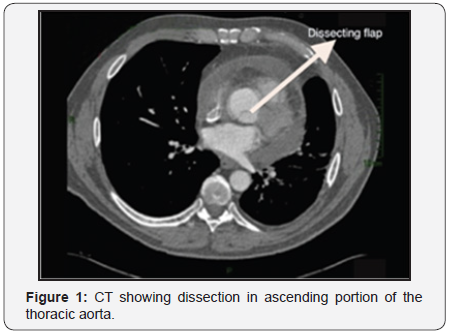

The international registry of aortic dissection (IRAD) lists the computed angiotomography (ATC) as the first most common diagnostic test on suspicion of aortic dissection (about 61%), followed by Transthoracic echocardiography and Transesophageal (ETT and ETE) (around 33%), magnetic resonance imaging (MRI) (around 2%), in addition to angiography corresponding to 4%. This reflects their availability and accessibility of these modalities [13] (Figure 1).

The chest x-ray in supine antero-posterior position can be useful, since in an initial assessment, despite having low sensitivity, shows signs that direct the diagnosis or the need for other tests [5]. These evidences are: widening of the mediastinum (>8cm); abnormal aortic contour; deletion of aortic button; orotracheal tube and trachea deviation to the right; source left bronchus depression; diversion of nasogastric tube to the right; extrapleural apical leakage; a density; fracture of the first and second ribs; obliteration of the space between the pulmonary artery and aorta; elevation and deflection to the right of the right main bronchus; hemothorax. The helical computed tomography (CT) of chest no cuts must be indicated after the fine interpretation of trauma mechanisms [3]. Is the most common initial examination because it is less invasive and allows quick diagnosis in emergency situations [14]. Is an excellent method for diagnosis to triage patients with suspected aortic injury, showing a sensitivity ranging from 93% to 100% and specificity of 87% to 100% [3,15,16] (Figure 2).